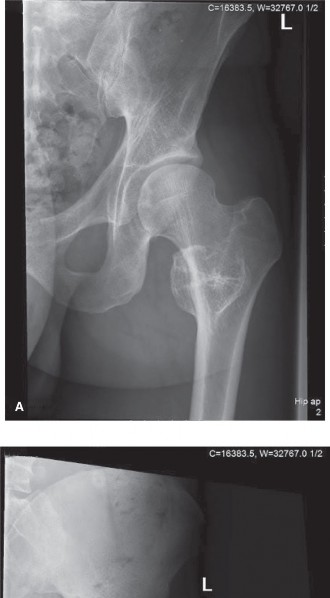

Initial imaging included standard anteroposterior and lateral plain radiographs of the left femur and knee. The radiographs revealed a large, lytic lesion centered within the metadiaphyseal region of the distal femur. The lesion demonstrated an aggressive radiographic appearance characterized by ill-defined margins and a wide zone of transition. Significant endosteal scalloping was present, accompanied by frank cortical destruction, particularly localized to the lateral cortex.

Within the radiolucent matrix of the lesion, areas of faint, irregular calcification were clearly identified. These calcifications exhibited the classic "rings and arcs" and "flocculent" morphology, which is highly pathognomonic for a chondroid matrix. A patchy and discontinuous periosteal reaction was observed, indicative of a biological process that is expanding rapidly enough to outpace the periosteum's ability to lay down mature reactive bone. While severe cortical thinning and erosion were evident, no complete pathological fracture was identified.